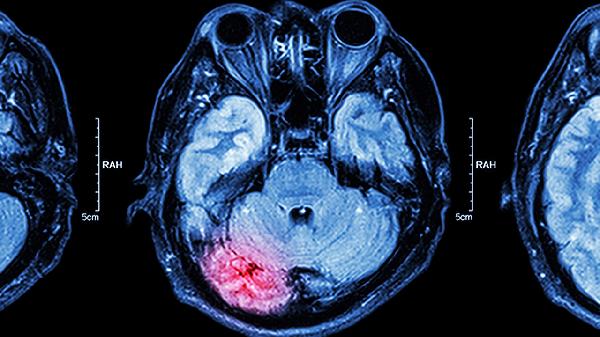

脑蛋白水解物片主要用于改善脑功能障碍相关疾病,如脑卒中后遗症、颅脑损伤恢复期、老年性痴呆等。该药物含有游离氨基酸和小分子肽,能通过血脑屏障促进脑细胞代谢修复。

5、缺氧性脑病

一氧化碳中毒、窒息等导致的缺氧性脑损伤可尝试用此药治疗。药物能减轻缺氧引起的脑细胞水肿,常配合依达拉奉注射液使用。治疗窗口期为发病后2-4周,超过3个月则疗效显著降低。